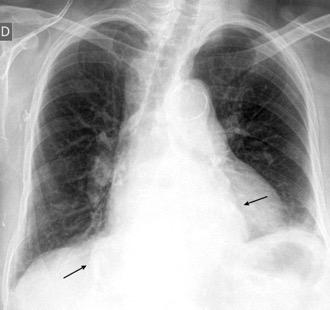

0,4% de casos de trauma. 80% lado izquierdo. Bilateral. 3%

Penetrante..63% 20-59%. Arma de fuego 15-32%. Arma blanca

Trauma cerrado. 37%

Tráfico Caída de gran altura

Aplastamiento toracoabdominal

Furak J et al. Diaphragm and transdiaphragmatic injuries. J Thorac Dis 2019

Accidente de tráfico

Rx: Niveles hidroaéreos en hemitórax izquierdo Desviación mediastínica Ausencia de intestino en abdomen. Configuración en reloj de arena del intestino herniado “Tubo nasogástrico”